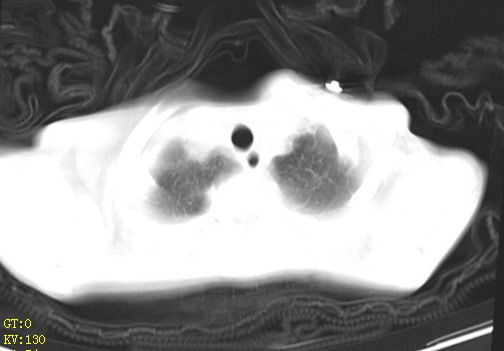

女,12岁,气促、咳嗽2天,3个月前查胸片示:两肺感染,急诊入院查ct,血常规等未检查。

双肺中下野不规则片絮状阴影,中外带明显,双侧胸腔少量积液,心影增大,心腔密度减低,隆突下及左侧气管旁见钙化淋巴结影,考虑双肺感染、心衰;建议结合临床除外h1n1并急性心衰,先心不能排除。

两肺多发片絮状模糊影,以下肺外带居多,内见支气管气像,纵膈窗未减影,两侧胸腔积液,心影增大,结合心超,支持重症肺炎,非常时期,甲型h1n1流感不排除。